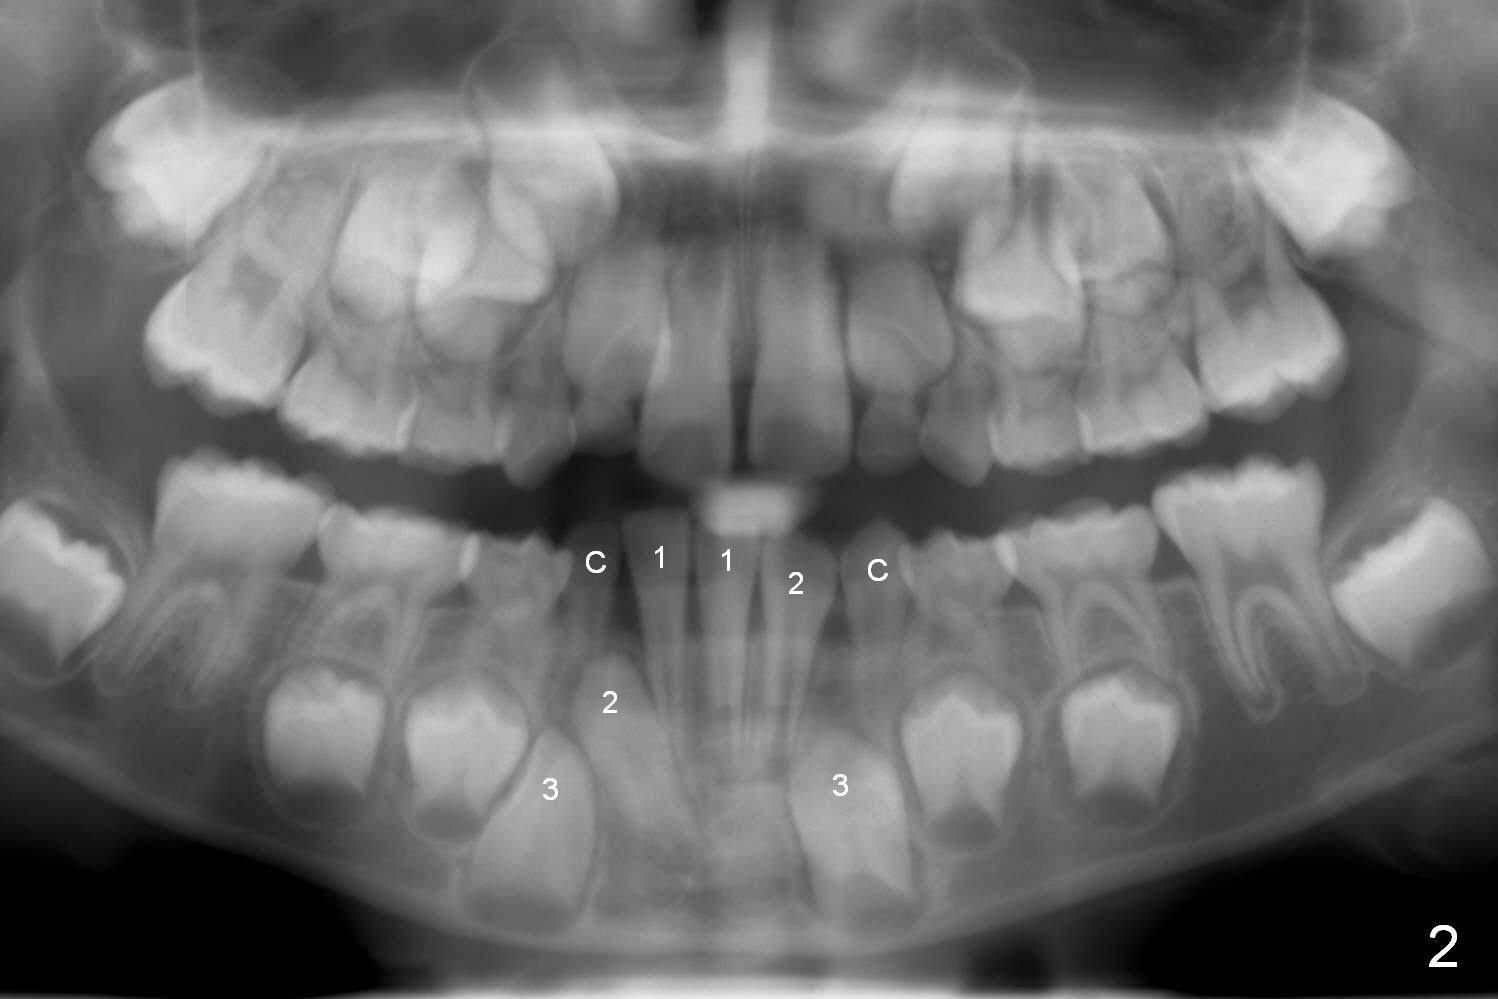

The lower right deciduous lateral incisor of a 5-year-old boy is congenitally missing (Fig.1). When he is 8 years old, the succedaneous tooth is unerupted (Fig.2). When the lower left canine (C) is exfoliated, extract LR C and LR 2 so that LR 3 has a chance to erupt normally.